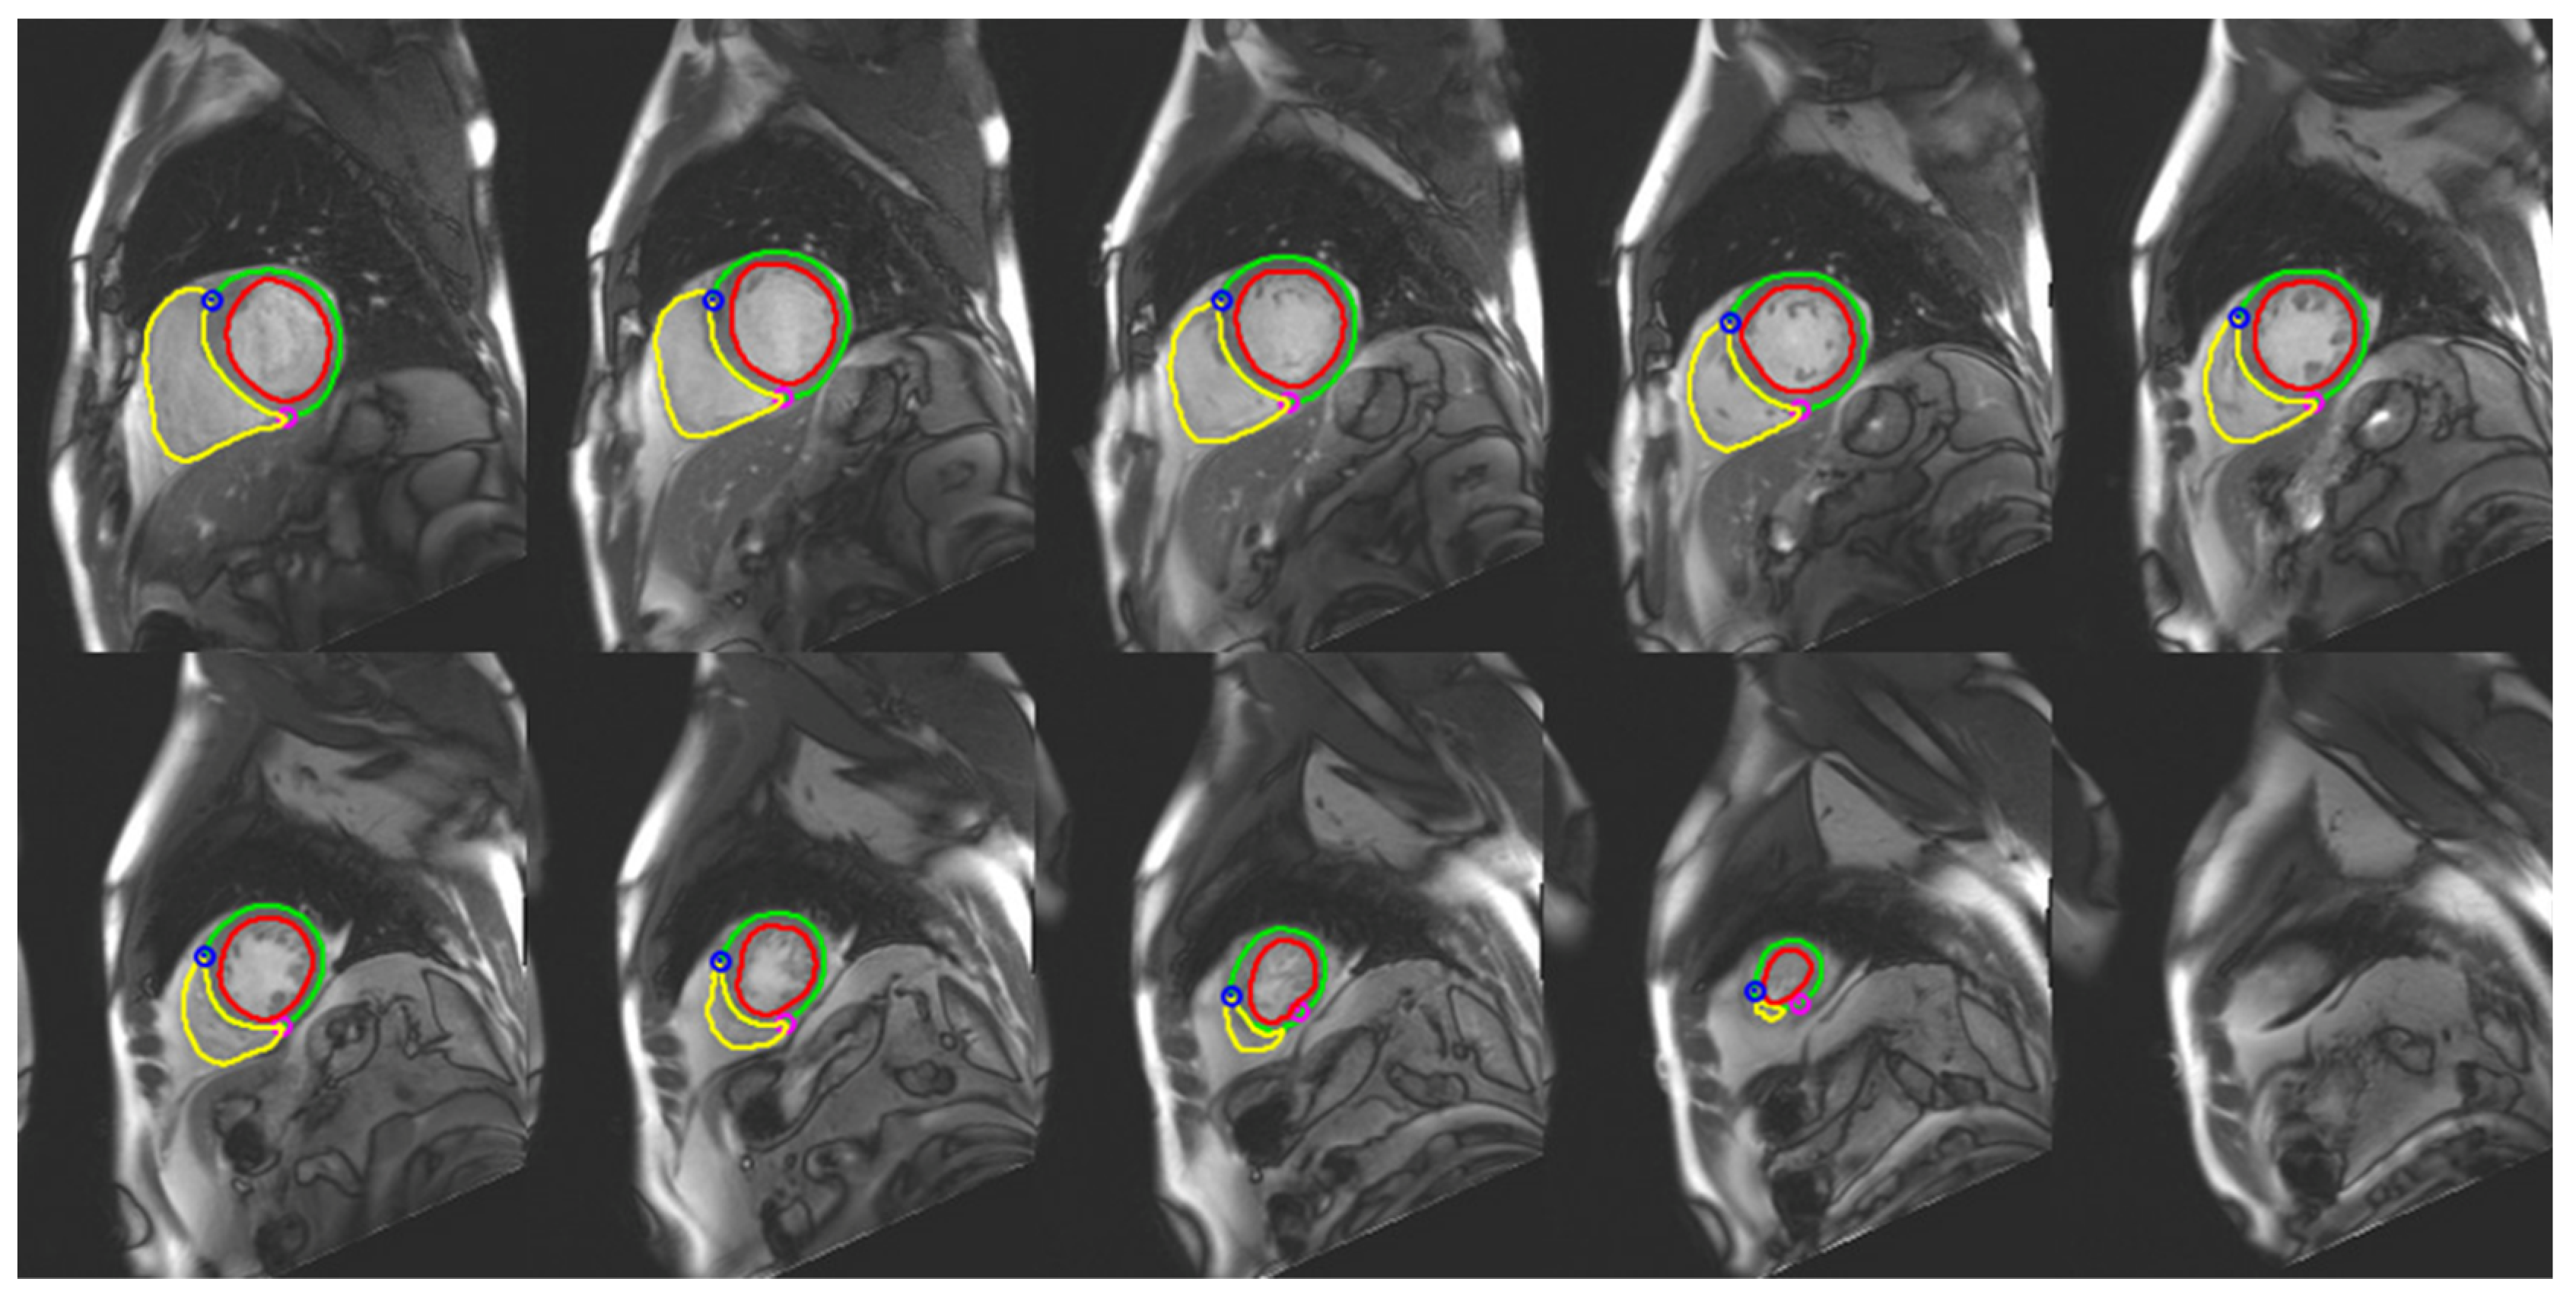

- Varga-Szemes, A.; Muscogiuri, G.; Schoepf, U.J.; Wichmann, J.L.; Suranyi, P.; De Cecco, C.N.; Cannao, P.M.; Renker, M.; Mangold, S.; Fox, M.A.; et al. Clinical feasibility of a myocardial signal intensity threshold-based semi-automated cardiac magnetic resonance segmentation method. Eur. Radiol. 2016, 26, 1503–1511. [Google Scholar] [CrossRef]

- Petitjean, C.; Dacher, J.N. A review of segmentation methods in short axis cardiac MR images. Med. Image Anal. 2011, 15, 169–184. [Google Scholar] [CrossRef] [PubMed]

- Suinesiaputra, A.; Bluemke, D.A.; Cowan, B.R.; Friedrich, M.G.; Kramer, C.M.; Kwong, R.; Plein, S.; Schulz-Menger, J.; Westenberg, J.J.; Young, A.A.; et al. Quantification of LV function and mass by cardiovascular magnetic resonance: Multi-center variability and consensus contours. J. Cardiovasc. Magn. Reason. 2015, 17, 63. [Google Scholar] [CrossRef]

- Bernard, O.; Lalande, A.; Zotti, C.; Cervenansky, F.; Yang, X.; Heng, P.A.; Cetin, I.; Lekadir, K.; Camara, O.; Gonzalez Ballester, M.A.; et al. Deep Learning Techniques for Automatic MRI Cardiac Multi-Structures Segmentation and Diagnosis: Is the Problem Solved? IEEE Trans. Med. Imaging 2018, 37, 2514–2525. [Google Scholar] [CrossRef]

- Bai, W.; Sinclair, M.; Tarroni, G.; Oktay, O.; Rajchl, M.; Vaillant, G.; Lee, A.M.; Aung, N.; Lukaschuk, E.; Sanghvi, M.M.; et al. Automated cardiovascular magnetic resonance image analysis with fully convolutional networks. J. Cardiovasc. Magn. Reason. 2018, 20, 65. [Google Scholar] [CrossRef]

- Tao, Q.; Yan, W.; Wang, Y.; Paiman, E.H.M.; Shamonin, D.P.; Garg, P.; Plein, S.; Huang, L.; Xia, L.; Sramko, M.; et al. Deep Learning-based Method for Fully Automatic Quantification of Left Ventricle Function from Cine MR Images: A Multivendor, Multicenter Study. Radiology 2019, 290, 81–88. [Google Scholar] [CrossRef]

- Li, Y.; Liu, Z.; Lai, Q.; Li, S.; Guo, Y.; Wang, Y.; Dai, Z.; Huang, J. ESA-UNet for assisted diagnosis of cardiac magnetic resonance image based on the semantic segmentation of the heart. Front. Cardiovasc. Med. 2022, 9, 1012450. [Google Scholar] [CrossRef] [PubMed]

- Wong, K.K.L.; Zhang, A.; Yang, K.; Wu, S.; Ghista, D.N. GCW-UNet segmentation of cardiac magnetic resonance images for evaluation of left atrial enlargement. Comput. Methods Programs Biomed. 2022, 221, 106915. [Google Scholar] [CrossRef] [PubMed]